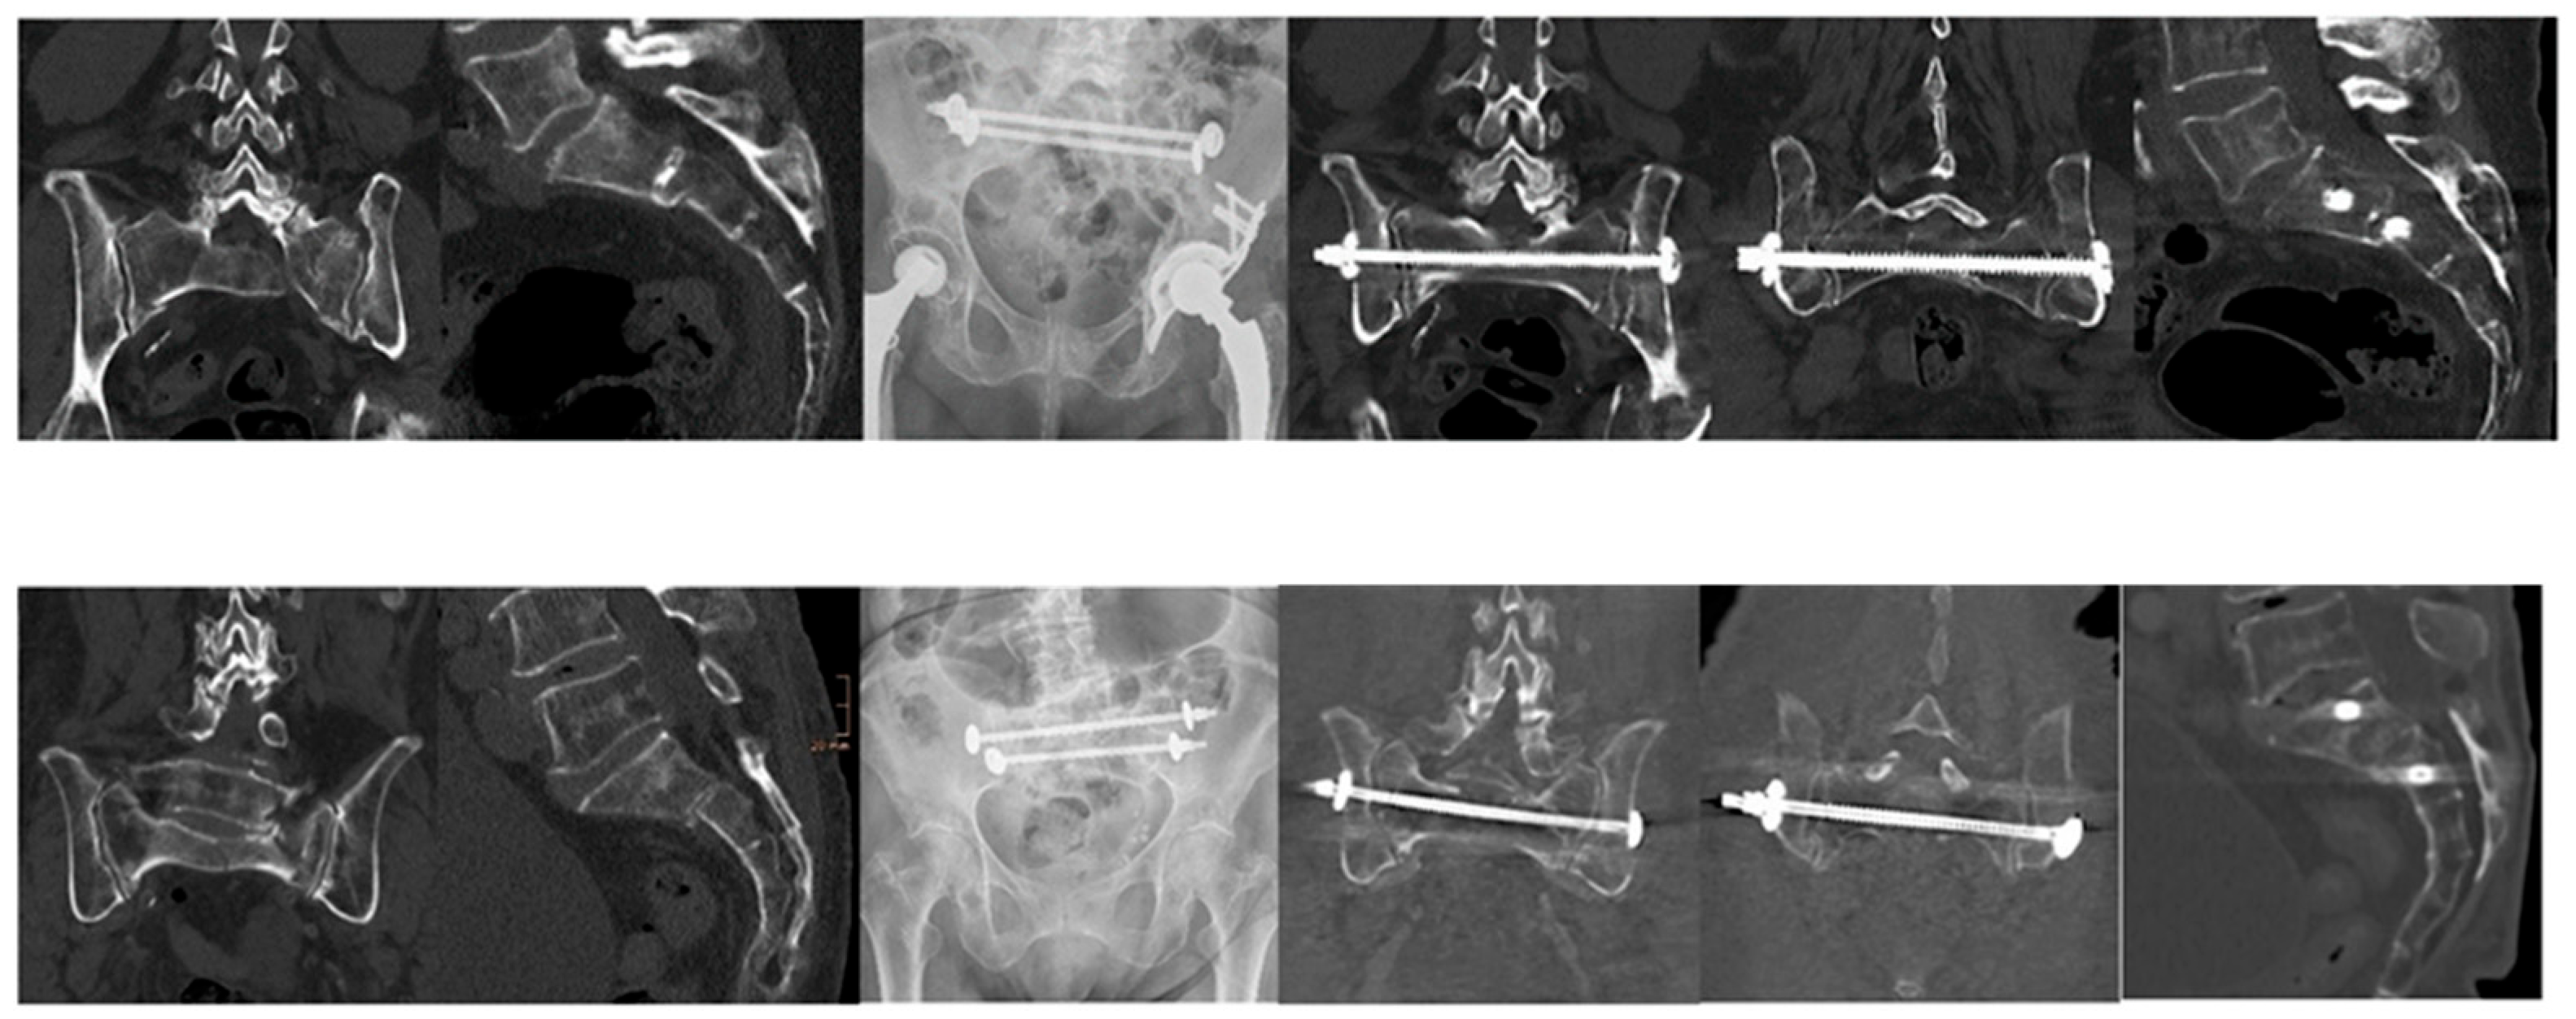

Importantly, radiographic assessment for implant loosening revealed no cases of loosening among the 31 patients with evaluable follow-up data, indicating high biomechanical integrity of the fixation constructs employed. Figure 1 shows two representative examples of H-shaped fractures with good healing demonstrated on CT after six months.

Figure 1. Two Clinical Examples: CT images on the left illustrate a displaced pelvic fracture with a comminuted zone in the lateral mass and an anterior angulation in the sagittal plane. The accompanying X-ray shows fixation using two transsacral bars (TSB). Follow-up CT images on the right, taken six months postoperatively, demonstrate satisfactory fracture consolidation.